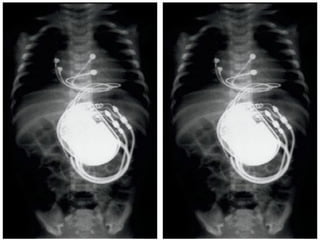

• São aparelhos grandes, e ficam com aspecto inestético. Modelos antigos

• Já os aparelhos desfibriladores modernos diferenciam bem arritmias de

contraturas musculares e o cirurgião cardíaco pode fazer implante

submuscular (da mesma maneira com que os cirurgiões plásticos colocam

próteses de silicones), de forma a que esse grande aparelho fique

praticamente imperceptível, mesmo em pessoas magras.

• Os desfibriladoressão indicados para prevenir a Morte Súbita Cardíaca, a parada cardíaca em pacientes que já tiveram alguma vez (prevenção secundária) ou em quem nunca teve (prevenção primária). • São considerados candidatos os pacientes que têm o coração muito fraco (Fração de Ejeção menor de 35%) ou moderadamente fraco (FEVE 35- 40%), mas com presença de arritmia grave (taquicardia ventricular) no holter ou em estudo eletrofisiológico. • São aparelhos grandes, e ficam com aspecto inestético. Modelos antigos tinham de ser implantados abaixo da pele para se evitar leituras frequentes de contraturas musculares levando o aparelho a interpretar como arritmias. • Já os aparelhos desfibriladores modernos diferenciam bem arritmias de contraturas musculares e o cirurgião cardíaco pode fazer implante submuscular (da mesma maneira com que os cirurgiões plásticos colocam próteses de silicones), de forma a que esse grande aparelho fique praticamente imperceptível, mesmo em pessoas magras. DESFIBRILADORES